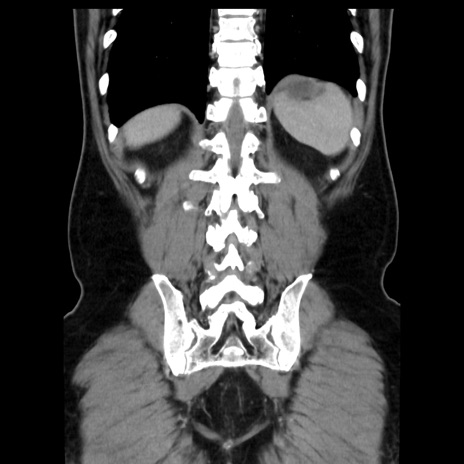

症例16(冠状断像)

【症例】 70歳代男性

【主訴】 腹痛、嘔吐

【現病歴】 約1ヶ月前より間欠的に腹痛と嘔吐あり、当院消化器内科を受診したところCTで多発する肝臓のLDAを指摘され、精査中であった。以降は消化器症状は安定していたが、2日前より嘔気と腹痛があり、同日より排便・排ガスが消失した。改善認めず、 本日、救急外来を受診した。

【既往歴】 大腸ポリープ切除後。

【身体所見】意識清明・会話良好、BT 36.3℃、BP 127/80mmHg、 P 80bpm、腹部:膨満あり、平坦・軟、上腹部正中および下腹部正中に圧痛あり、反跳痛なし、筋性防御なし。

【データ】WBC 7200、CRP 0.77